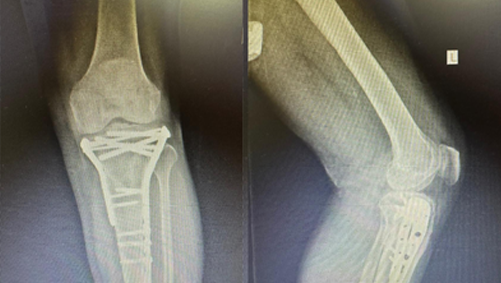

Patient underwent open reduction & internal fixation for Tibial condyle fracture 4 years back